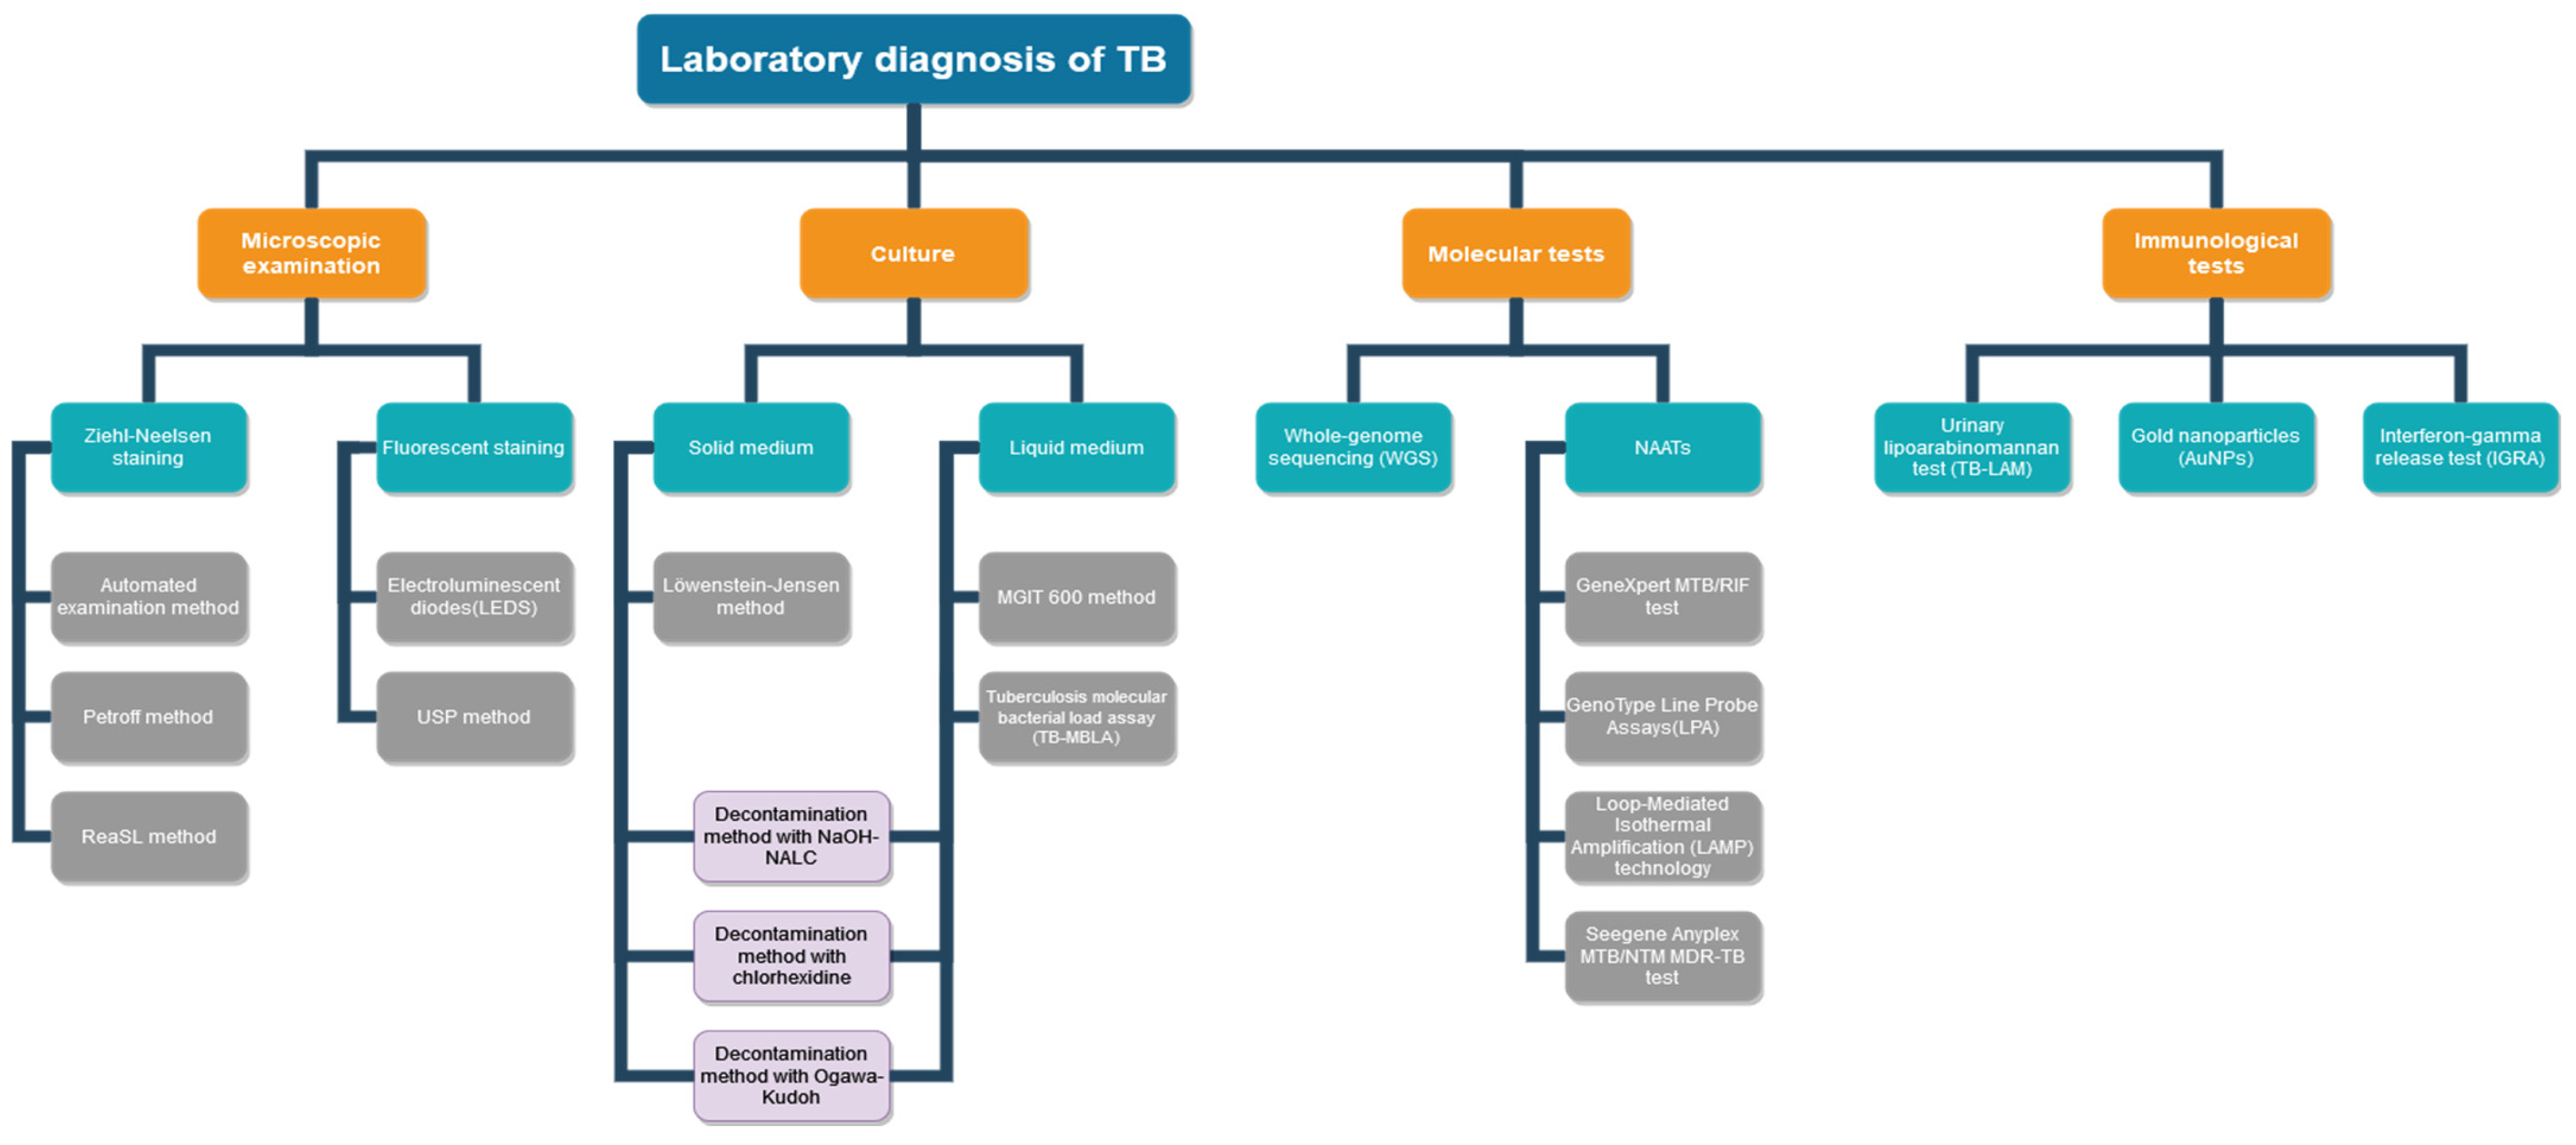

Evolution of Laboratory Diagnosis of Tuberculosis

1. Introduction

2. Microscopic Diagnosis of TB

2.1. Microscopic Examination with Ziehl–Neelsen Staining

2.2. Microscopic Examination with Fluorescent Staining

2.3. The Fluorescent Microscopy Method with Electroluminescent Diodes (LEDs)

2.4. Automated Microscopic Examination Method

2.5. USP Method (Modified Auramine–Rhodamine Ziehl–Neelsen)

2.6. Petroff Method

2.7. ReaSLR Method

3. Mycobacterial Culture in TB Diagnosis

3.1. Lowenstein–Jensen Method (LJ)

3.2. MGIT 960 Technology

3.3. Decontamination Method with NaOH-NALC

3.4. Tuberculosis Molecular Bacterial Load Assay (TB-MBLA)

3.5. The Method of Decontamination with Chlorhexidine

3.6. Decontamination Method with Ogawa-Kudoh

4. Molecular Methods

4.1. Conventional Nucleic Acid Amplification Tests (NAAT)

4.1.1. GenoType Line Probe Assays (LPA)

4.1.2. Multidrug-Resistant Tuberculosis (MDR-TB)

4.1.3. Extensively Drug-Resistant Tuberculosis (XDR-TB)

4.2. Methods Based on Real-Time Genetic Amplification Technology RT-PCR GeneXpert MTB/RIF

4.3. Loop-Mediated Isothermal Amplification (LAMP) Technology

4.4. PCR Multiplex Seegene Anyplex MTB/NTM MDR-TB

4.5. WGS Sequencing (Whole-Genome Sequencing)

5. Diagnostic immunological tests

5.1. Urinary Lipoarabinomannan Test (TB-LAM)

5.2. Gold Nanoparticles (AuNPs)

5.3. Interferon-Gamma Release Tests (IGRA)

6. Conclusions